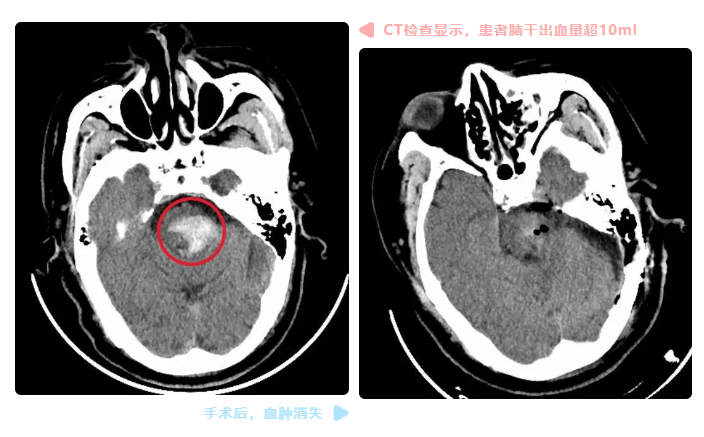

“脑部CT检查显示,患者脑干出血量超过10ml,必须立即以手术清除血肿。”神经外科主任蔡利介绍,脑干素有“生命禁区”之称,其中密集排列着颅神经的核团和肢体与大脑联系的上下传导束,一旦受损后果及其严重。因此脑干出血具有起病、病情凶险、预后较差的特点,是所有脑血管病中病死率及致残率最高、预后最差的一类脑血管病变,出血量超10ml则是该病最严重的病情级别,患者死亡率接近100%。

CT检查显示,陆先生脑干出血状况已完全解除,脑部也未有损伤。